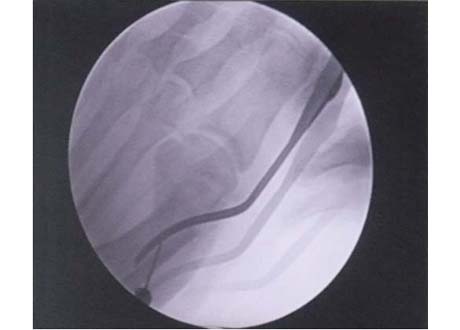

Figure 8

Blade used to cut tight band holding toe tilted (Lateral Release)